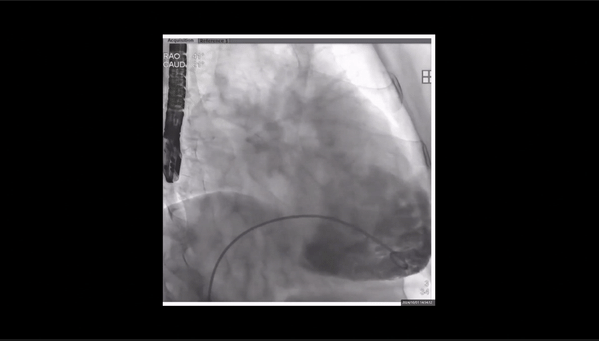

術前右室造影

夾持件位置確認

室間隔位置確認

瓣膜釋放